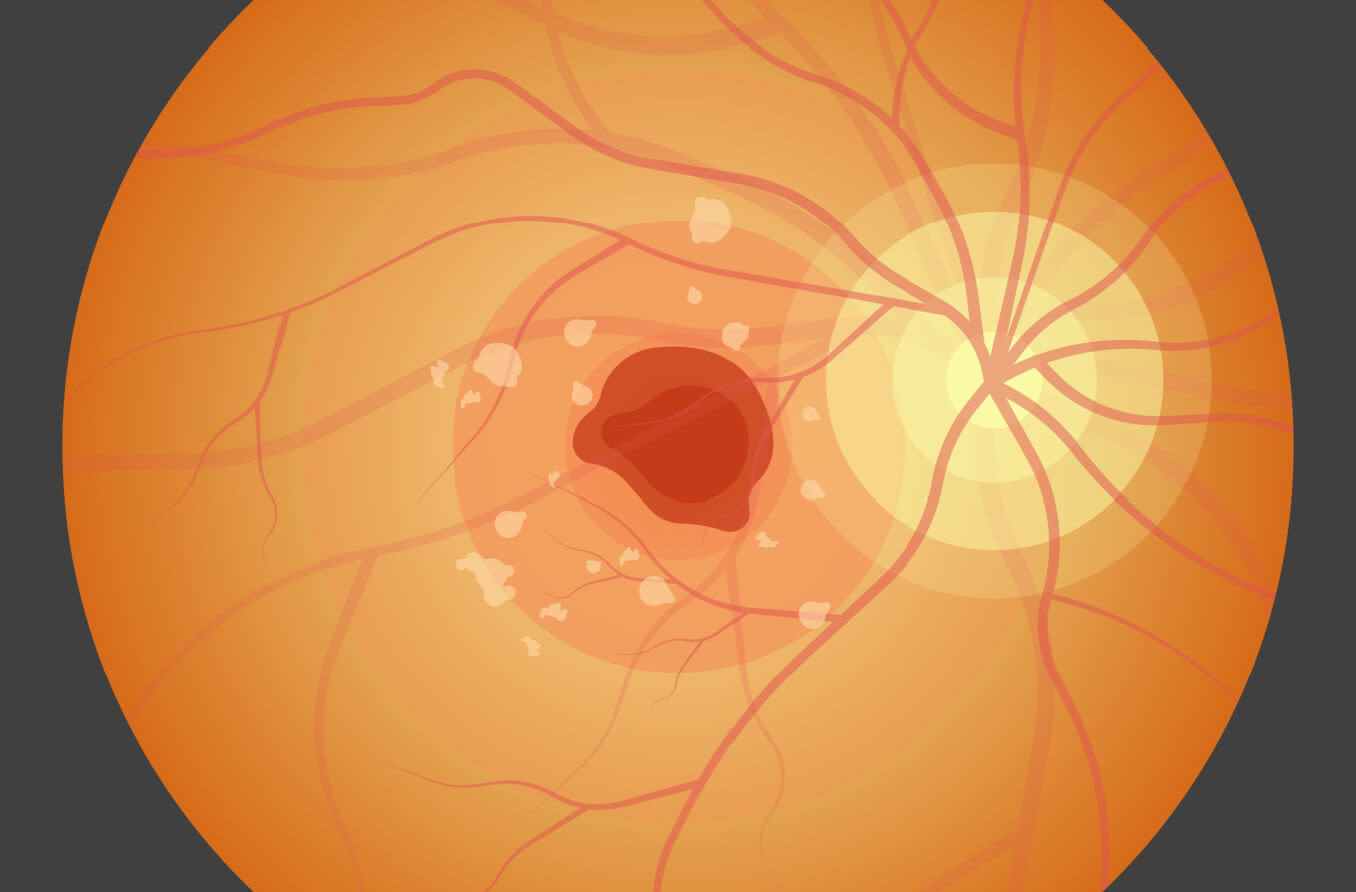

A doença de Stargardt é diagnosticada pela presença de pequenas manchas amareladas de tecido em deterioração (drusas) descamadas da cobertura colorida ou externa da retina (epitélio pigmentar da retina). A perda progressiva da visão eventualmente leva à cegueira na maioria dos casos.

Os sintomas da doença de Stargardt podem incluir visão embaçada ou distorcida, incapacidade de ver com pouca luz e dificuldade em reconhecer rostos familiares. Nos estágios finais de Stargardt, a visão das cores também pode ser perdida.